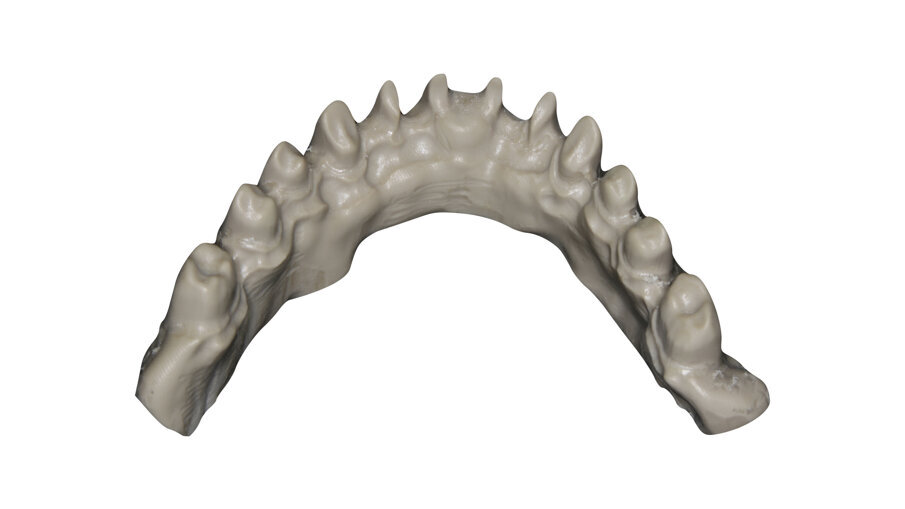

Another common situation is a full mouth restoration over implant. It is well known that the big issue is chipping and delimitation of the ceramics, due to the high forces applied in the patient with dental implants. In regards to this problem, the combination of rigid materials to support the connectors and resilient materials to absorb the shock and, at the same time, allow easy fixation, make the use of resin based blocks the logical choice for this kind of restoration (Figs. 6-8).

Fig. 6: Zirconia thimble framework and BRILLIANT Crios bridges for extra oral bonding.

Fig. 7: Zirconia bridges ready to be screwed.

Fig. 8: Upper and lower bridges in the mouth.